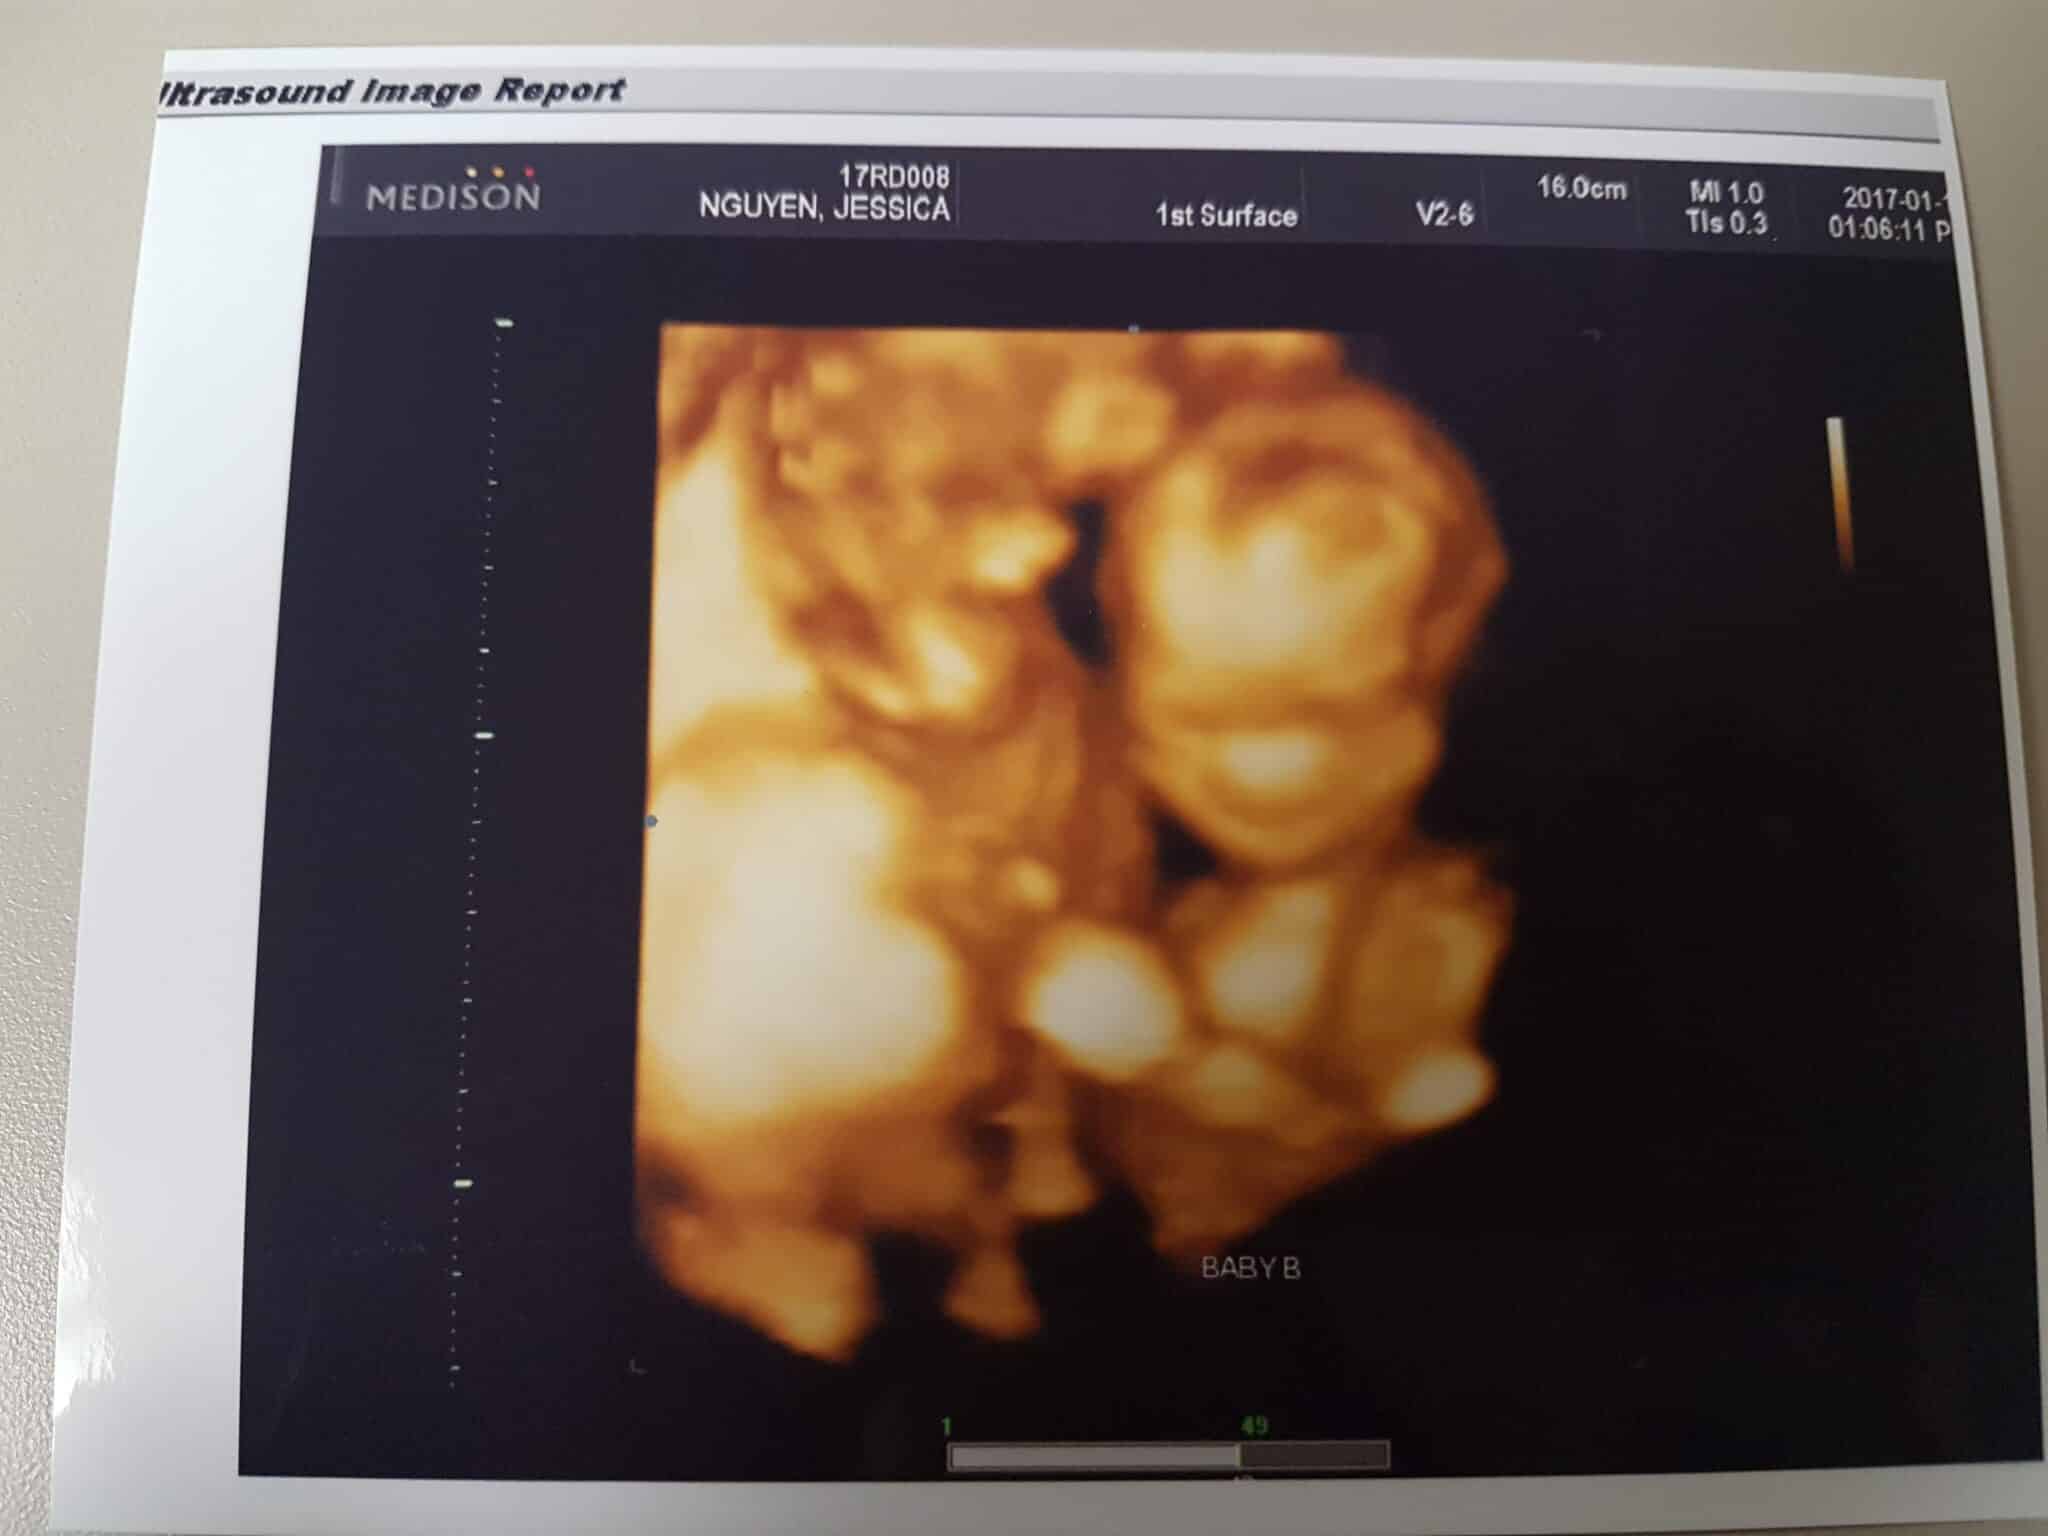

Ultrasound Photos at 18 Weeks Pregnant With Twins